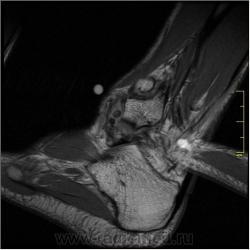

1. По "прямой рентгенограмме" я высказал-бы предположение о наличии субхондрального склероза в области дистального эпифиза б/берцовой кости - желтые стрелки, отметил - бы "окостенение" мягкотканного компонента - красная стрелка.

2. По "боковой рентгенограмме" при анализе передних отделов - отметил - бы окостенение мягкотканных компонентов - зеленые стрелки, высказал - бы "недоверие" передне-нижнему контуру дистального эпифиза б/берцовой кости. Возможно отметил, а возможно и нет некоторый субхондральный склероз по заднему коннтуру ладьевидной кости - красные стрелки.

Я считаю, что присутствуют добавочные кости голеностопного сустава: os trigonum, os talus secundarius, os subfibulare, окруженные выпотом, вероятно, реактивного характера в результате избыточной нагрузки.

Еще вопрос. Что за дефект эпифиза?

Я тоже считаю, что есть деформация края суставной поверхности. Может быть, в результате профессиональной деятельности. В любом случае, к клинической симптоматике это отношения наверняка не имеет.

Все-таки я считаю, что причина болезни до конца не установлена. Некоторые вопросы остались без ответа. С эпифизом б/б кости не все ясно.